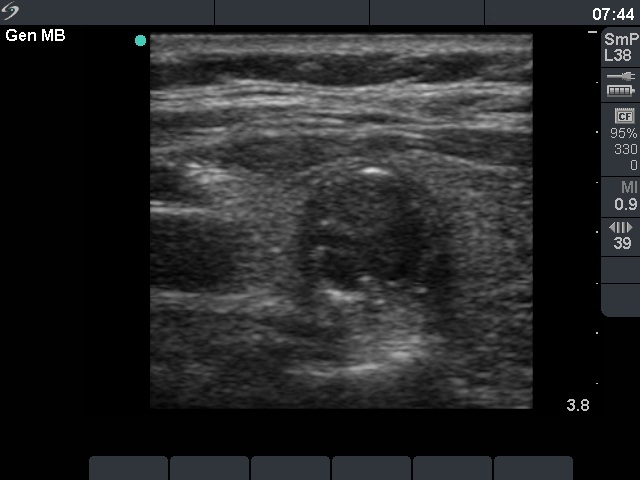

Benign hyperplastic nodule (histological diagnosis) - case 80

There were multiple foci of coarse calcification in this case. Note that acoustic shadowing is complete only at the edges of the lesions.